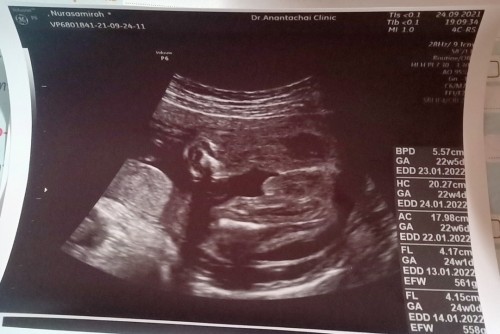

ภาพคล้ายกันเลยคะน่าจะผู้ชายนะคะ บ้านนี้ผู้ชายคะท้องแรกคะ🥰

ชายเหมือนกันค่ะคนนี้นอนจู๋โด่ให้ลุงหมอเห็นชัดเลยค่ะ14+3w

ชายค่ะแม่ ไข่น้องโตมาเชียว😅 ทีมลูกชายเหมือนกันค่ะ

เหมือนจะเห็นไข่นะคะ แม่ บ้านนี้โชว์จู๋มาเลย

ผู้ชาย100%เลยคะไข่กลมๆ ลูกชายเหมือนกันคะ

ผู้ชายค่ะแม่ น้องมีจู๋เหมือนกันเลย😂

ผู้ชายค่ะ น้องพกมาเยอะเลยค่ะ 😄

ผช จร้า น้องมีช้างน้อยยย 😁

14+3w ลุงหมอบอกชายโชว์จู๋เลย